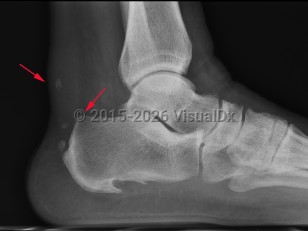

Achilles tendinosis / tendinopathy is tendon thickening in the region approximately 2-6 cm proximal to tendon insertion and is thought to be caused by poor blood supply and anaerobic degeneration of the cartilage.

Insertional Achilles tendonitis is pain and tendon thickening at insertion of the Achilles tendon, wherein repetitive trauma leads to inflammation followed by cartilaginous, bony metaplasia.

Haglund deformity is enlargement of the posterosuperior tuberosity of calcaneus. Retrocalcaneal bursitis is inflammation of the space between the anterior aspect of Achilles tendon and posterior aspect of calcaneus.